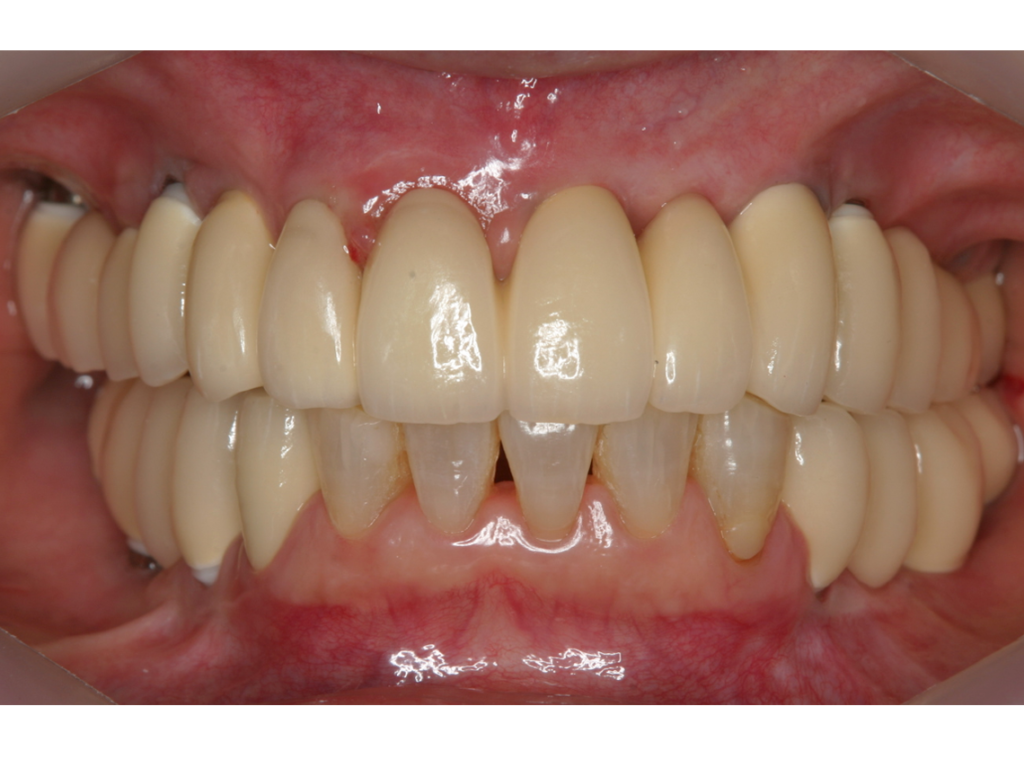

4.最終補綴物装着(2008年)

5.術後14年経過(2022年)

6.術後17年経過(2025年)

インプラント埋入部の骨レベルは埋入時と変わらず、患者様ご自身のメンテナンスも良好で、経過は非常に良く、満足されています。